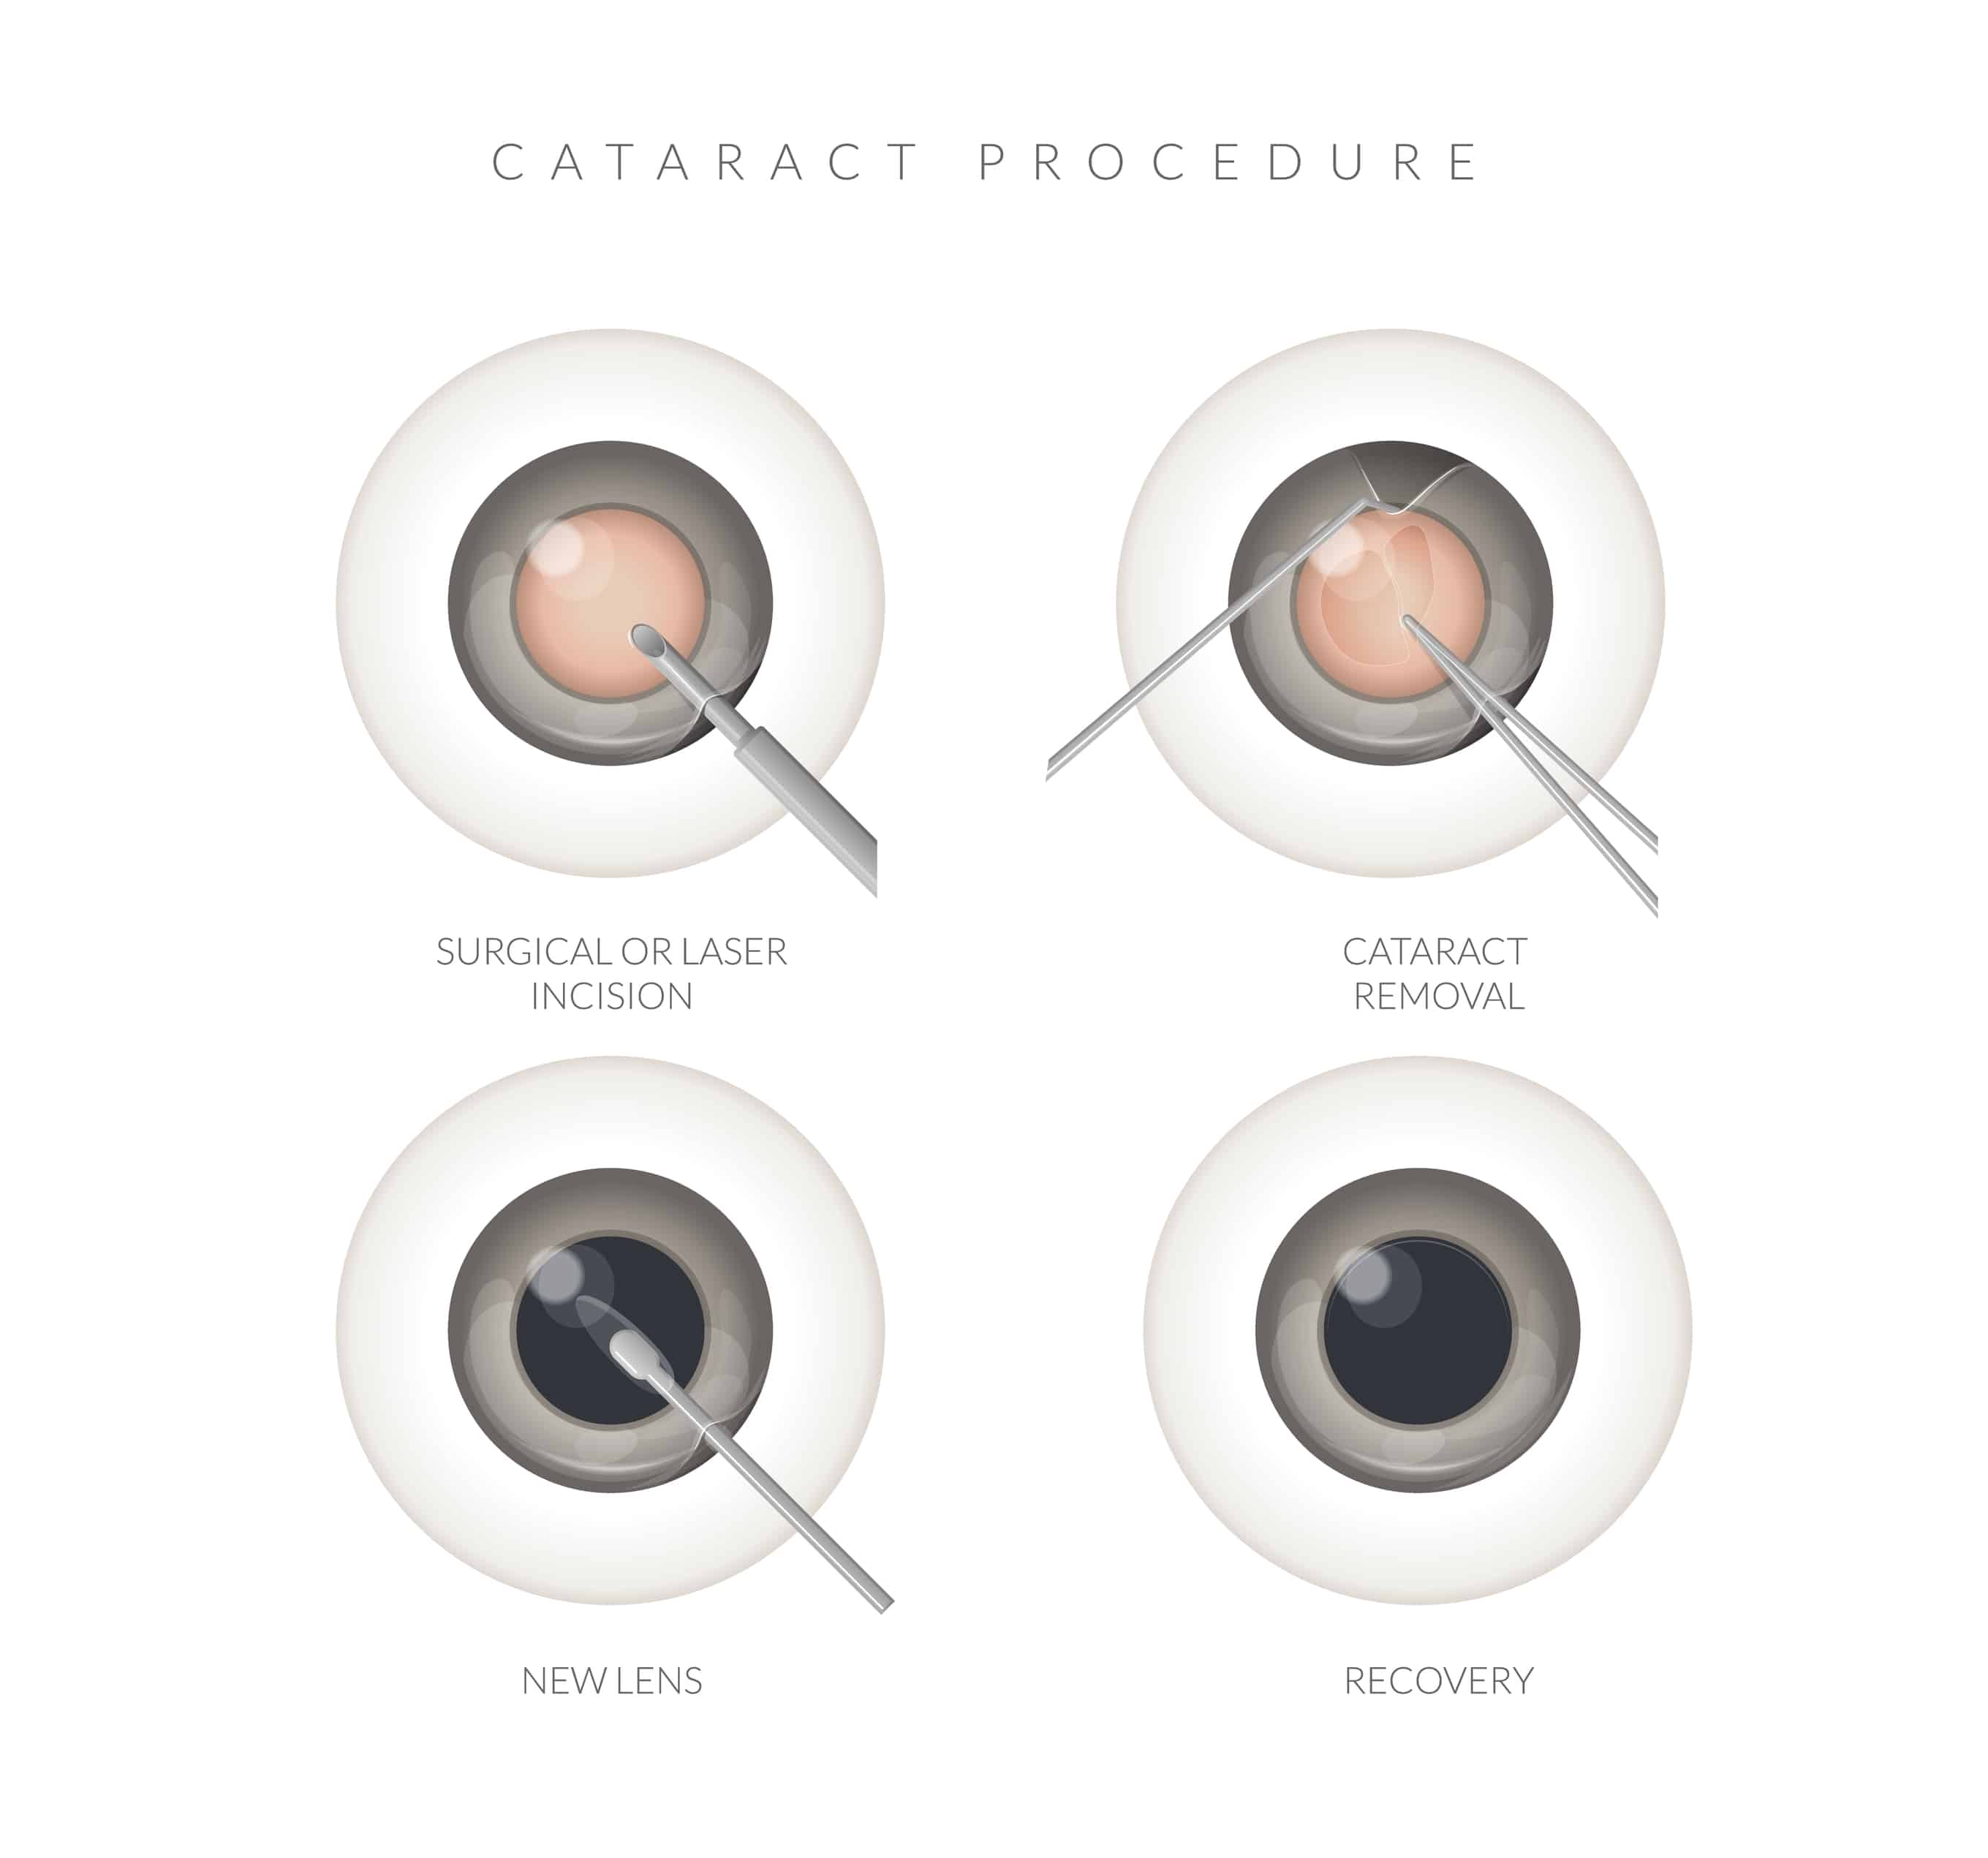

The only effective treatment for a cataract is surgical removal of the cloudy lens and replacement with a clear artificial lens called an intraocular lens (IOL). Cataract surgery is one of the safest and most commonly performed procedures in medicine today, with approximately 3 million surgeries performed each year in the United States. According to the American Society of Cataract and Refractive Surgery, more than 98% of patients experience successful improvement in vision following surgery.

Both techniques remove the cloudy lens and replace it with an artificial lens implant. The difference lies in how certain critical steps of the procedure are performed.

Phacoemulsification is considered the traditional or standard method of cataract surgery. During this procedure:

- A small incision is made in the cornea using a precise surgical blade.

- A circular opening is created in the capsule (the thin “bag” that holds the lens).

- An ultrasound probe is inserted to break up the cataract into tiny fragments.

- The fragments are gently suctioned out.

- A foldable intraocular lens is inserted through the same small incision and positioned inside the capsule.